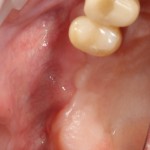

Имплантация и остеопластика: вместе или врозь? Часть II плюс Ankylos, плюс Geistlich